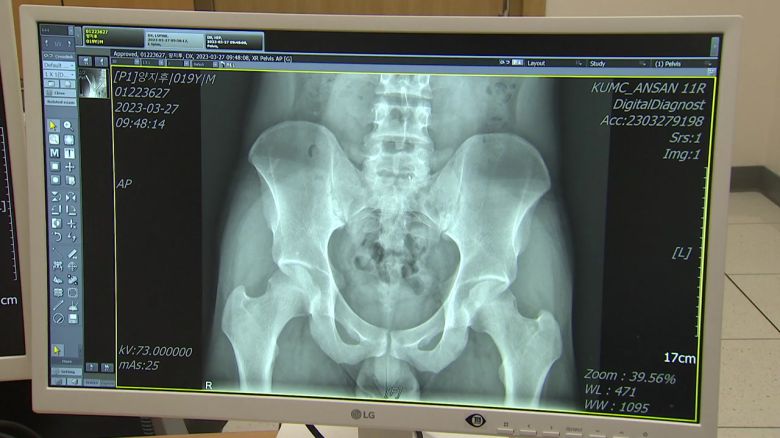

알고 보니 양 씨는 강직성 척추염을 앓고 있었던 겁니다.

강직성 척추염은 면역에 문제가 생겨 척추와 골반에 통증이 나타나는 만성 염증성 관절염입니다.

만약 방치한다면 척추의 유연성이 떨어지고 허리를 숙이거나 젖히는 동작 자체가 어려워질 정도로 구조적 문제가 생길 수도 있습니다.

[강은송 / 고대안산병원 류마티스내과 교수 : 뱀부스파인(대나무 모양 척추)이라는 것까지 진행할 수 있는데요. 그런 경우에 환자분께서 척추 관절의 가동 범위 자체가 거의 움직여지지 않아서 누웠다가 일어나는 데도 부축이 필요할 정도가 될 수 있고요.]